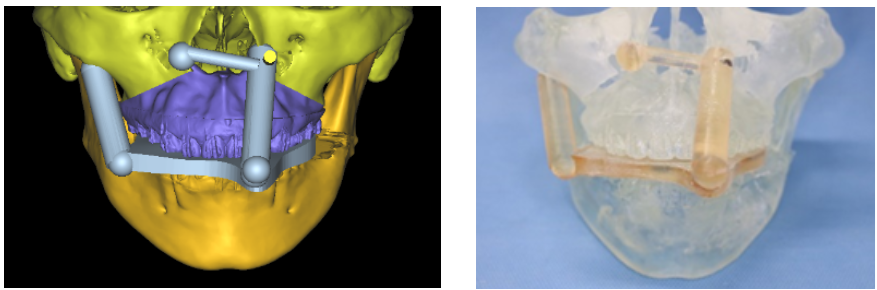

顎変形症とは、極端な上下顎骨の位置異常によるもので、歯科矯正治療単独では治療が困難な疾患です。症状としては摂食障害、発音障害、審美障害があります。治療は、手術によって上下顎骨を適切な位置に移動し、咬み合わせをつくっていきます。手術前・後には当科と提携している矯正歯科医による歯科矯正治療を行います。当科ではCT検査から手術シミュレーションを行い、手術前に上下顎骨の3Dモデルを作製して実際に位置移動を行って手術が適切にできるかどうか評価し、手術シミュレーションの再現性を確実なものとしています。自費治療による歯科矯正治療に対応した手術(サージェリーファースト)も行っています。

手術シミュレーション

実物大臓器立体モデルによる手術シミュレーション